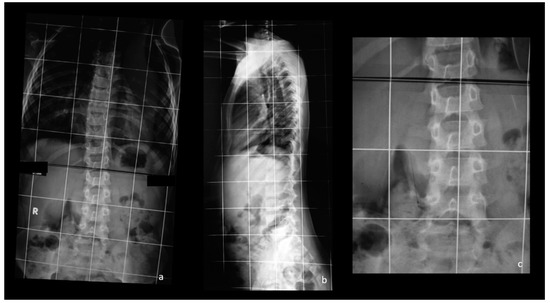

| Surgery (n) | N/A | 4 (15%) | 5 (29%) | 0.4 |